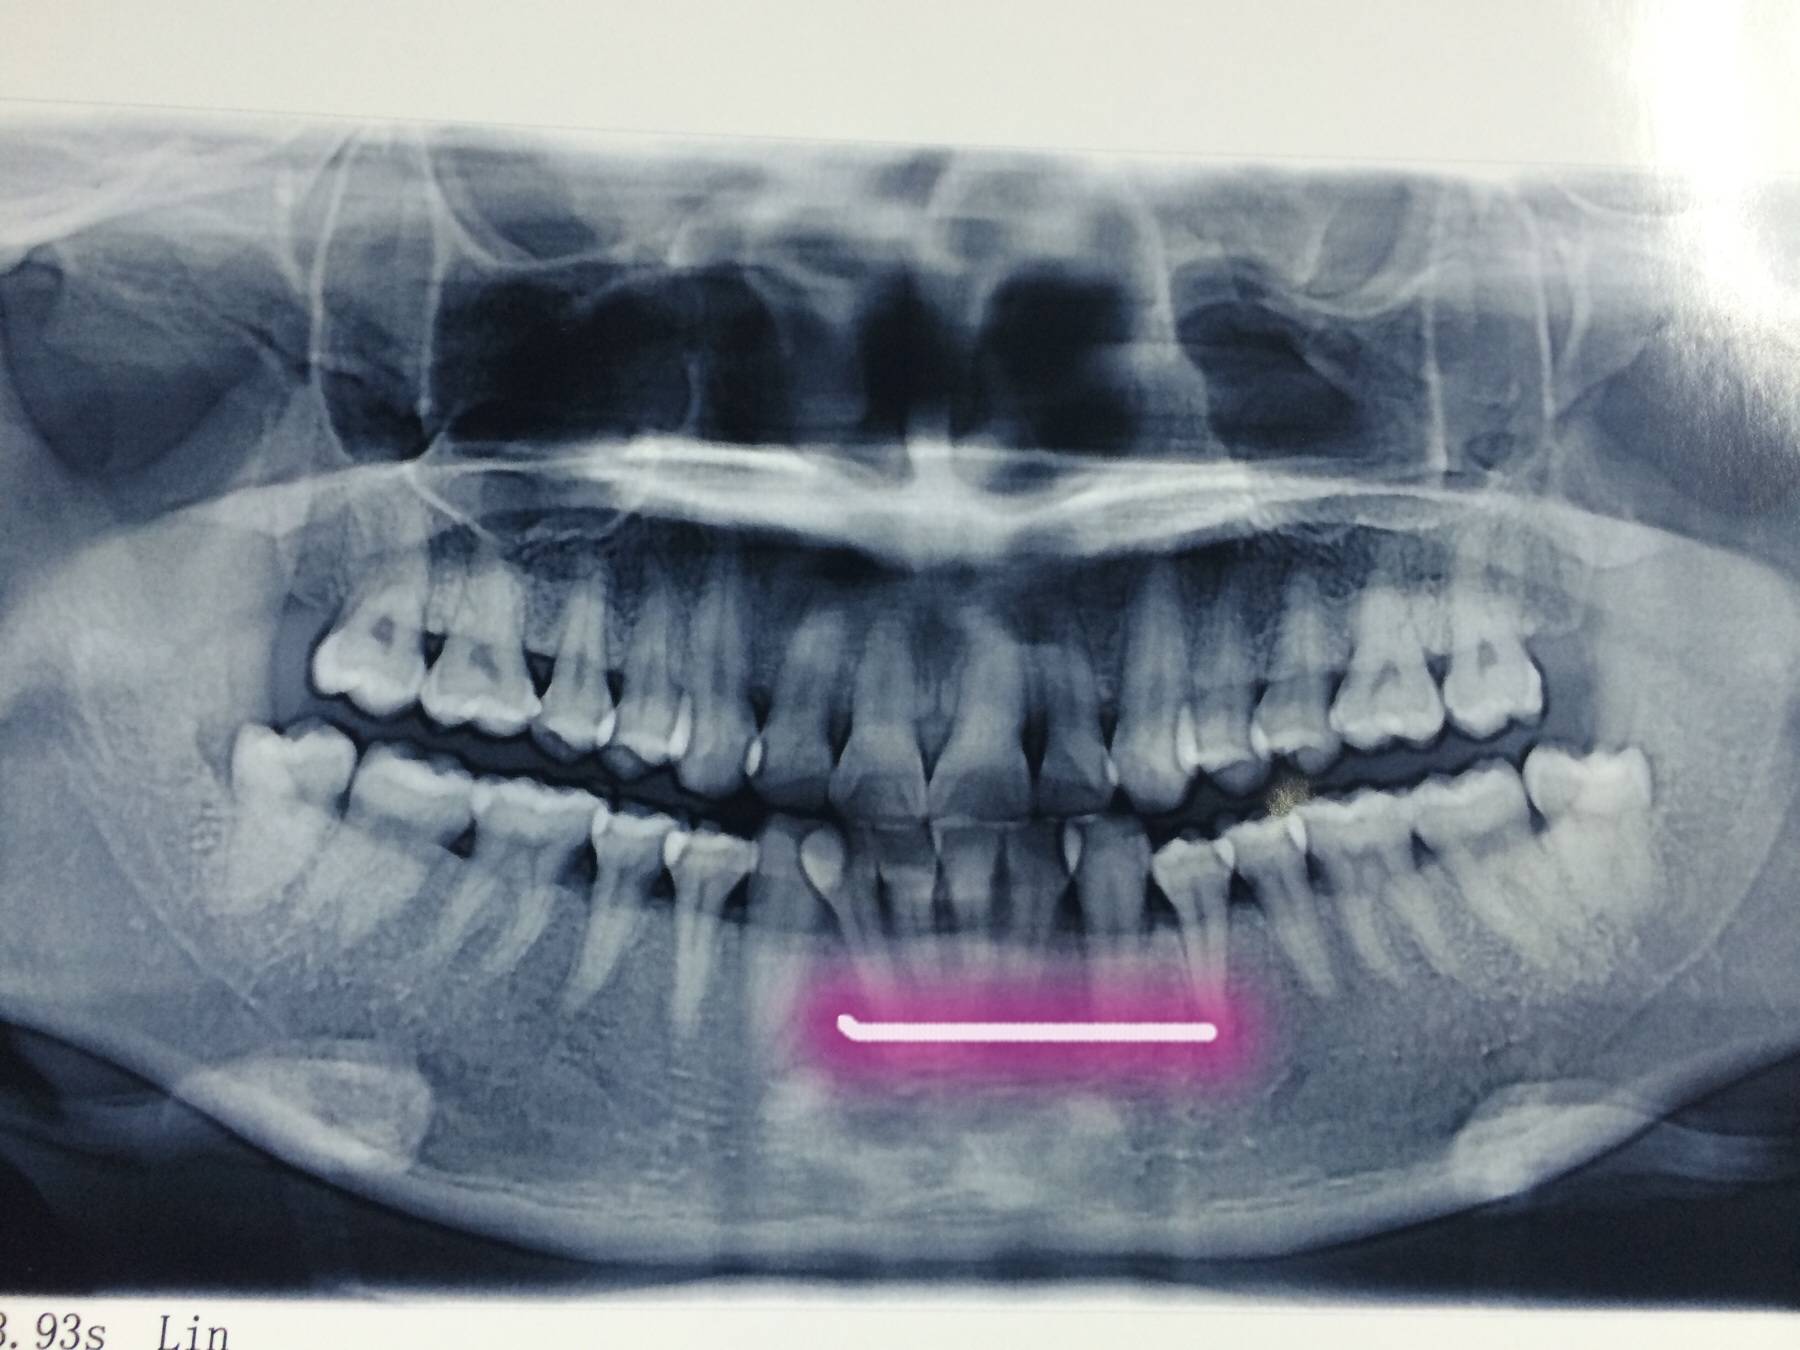

最近牙齿总是出血,特别是半夜醒来后,吐出来的都是唾液和血,医生说有炎症和结石,要我吃药后再洁牙,再微创,我滴天啦,哎,说是狼引起的,有洁牙得?告诉我哈,有什么不舒服没有,下面是我今天拍片看的牙齿,说下面4颗容易掉